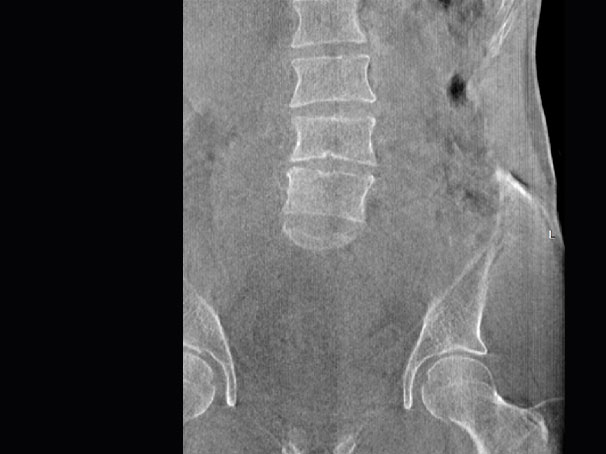

腰椎

FOV 250mm

FOV 350mm